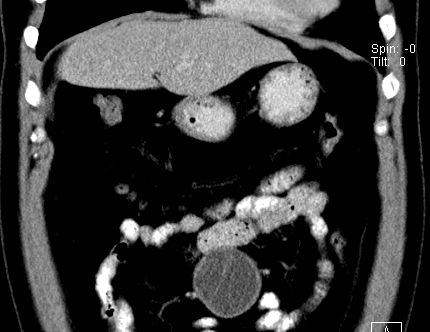

(腹腔)神经鞘瘤

男,48岁,间断性下腹不适1年。

手术探查

:距回盲部28厘米处肠系膜根部可见5*7cm左右包块,质中等硬度,活动度尚可,肝、胆、胰、脾肾未见明显异常。

病理

:(腹腔)

神经鞘瘤

,伴出血、坏死及囊性变,伴淋巴结反应性增生。

免疫组化结果

:sma(-), desmin(-), cd117(-), s-100(+++), nf(-),vimentin(+++).